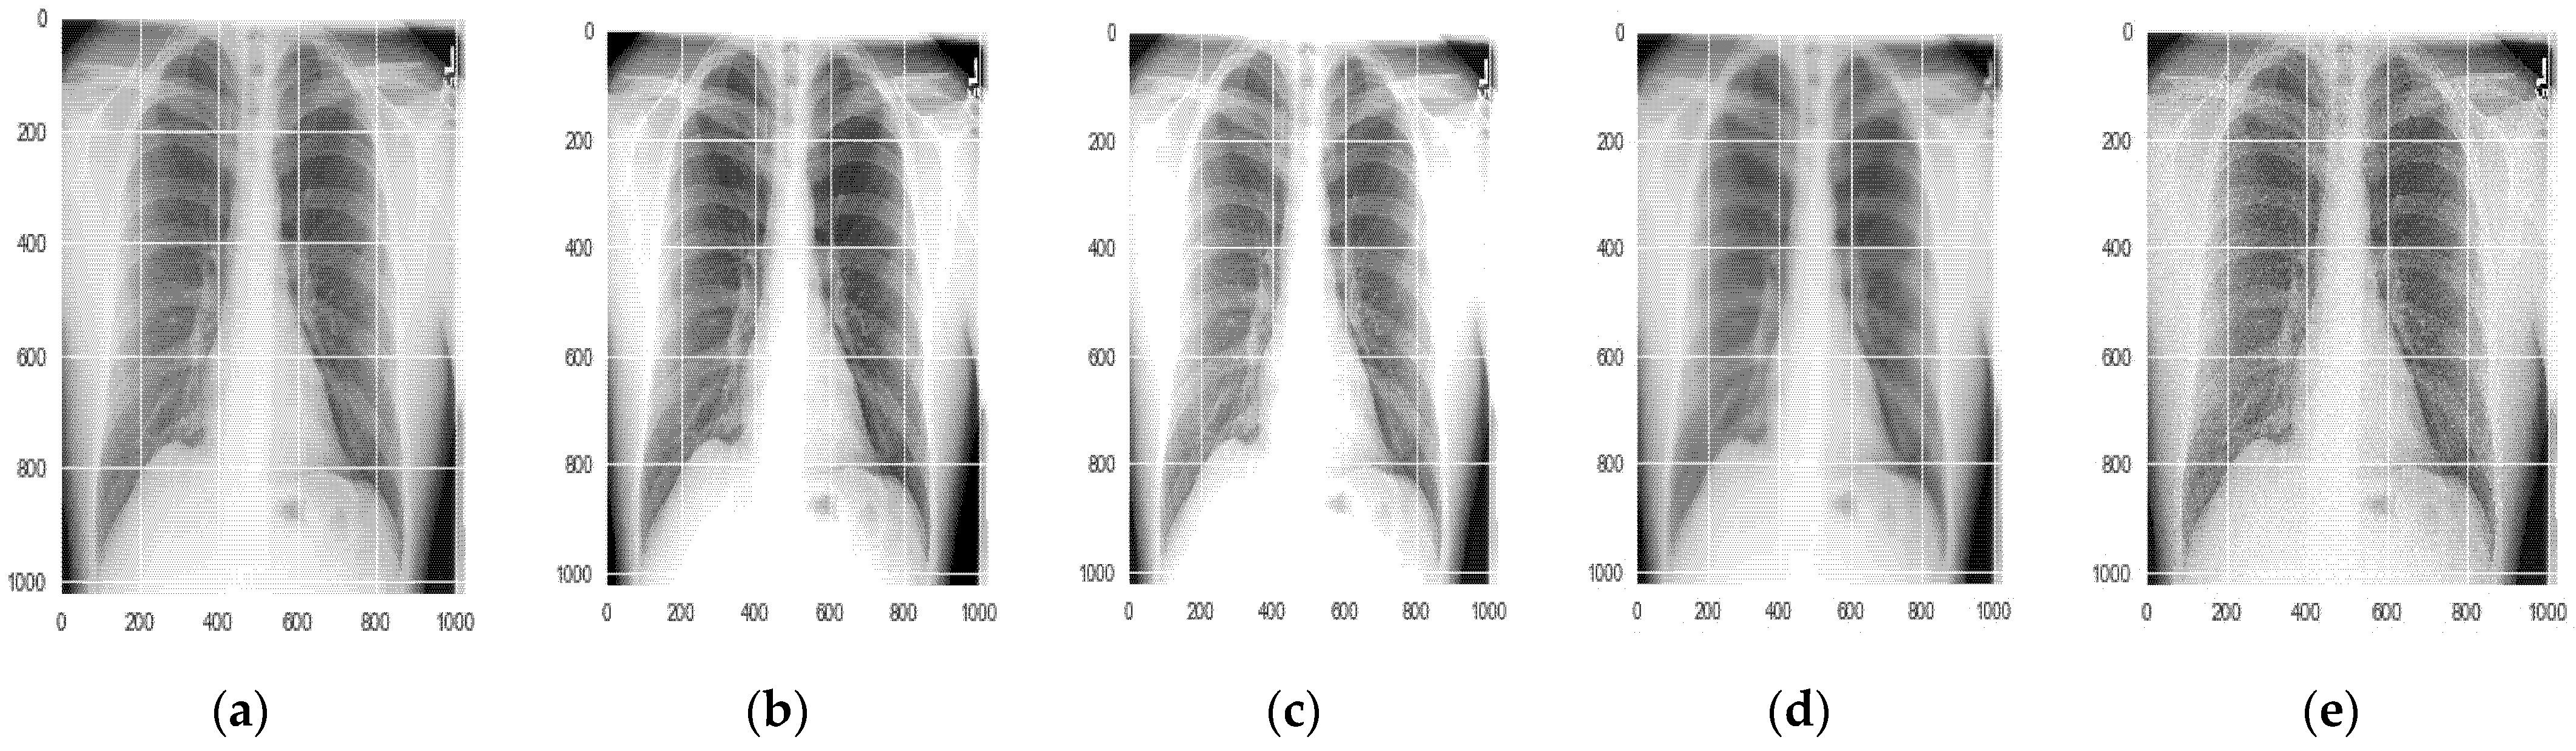

5.1.1. Data Augmentation